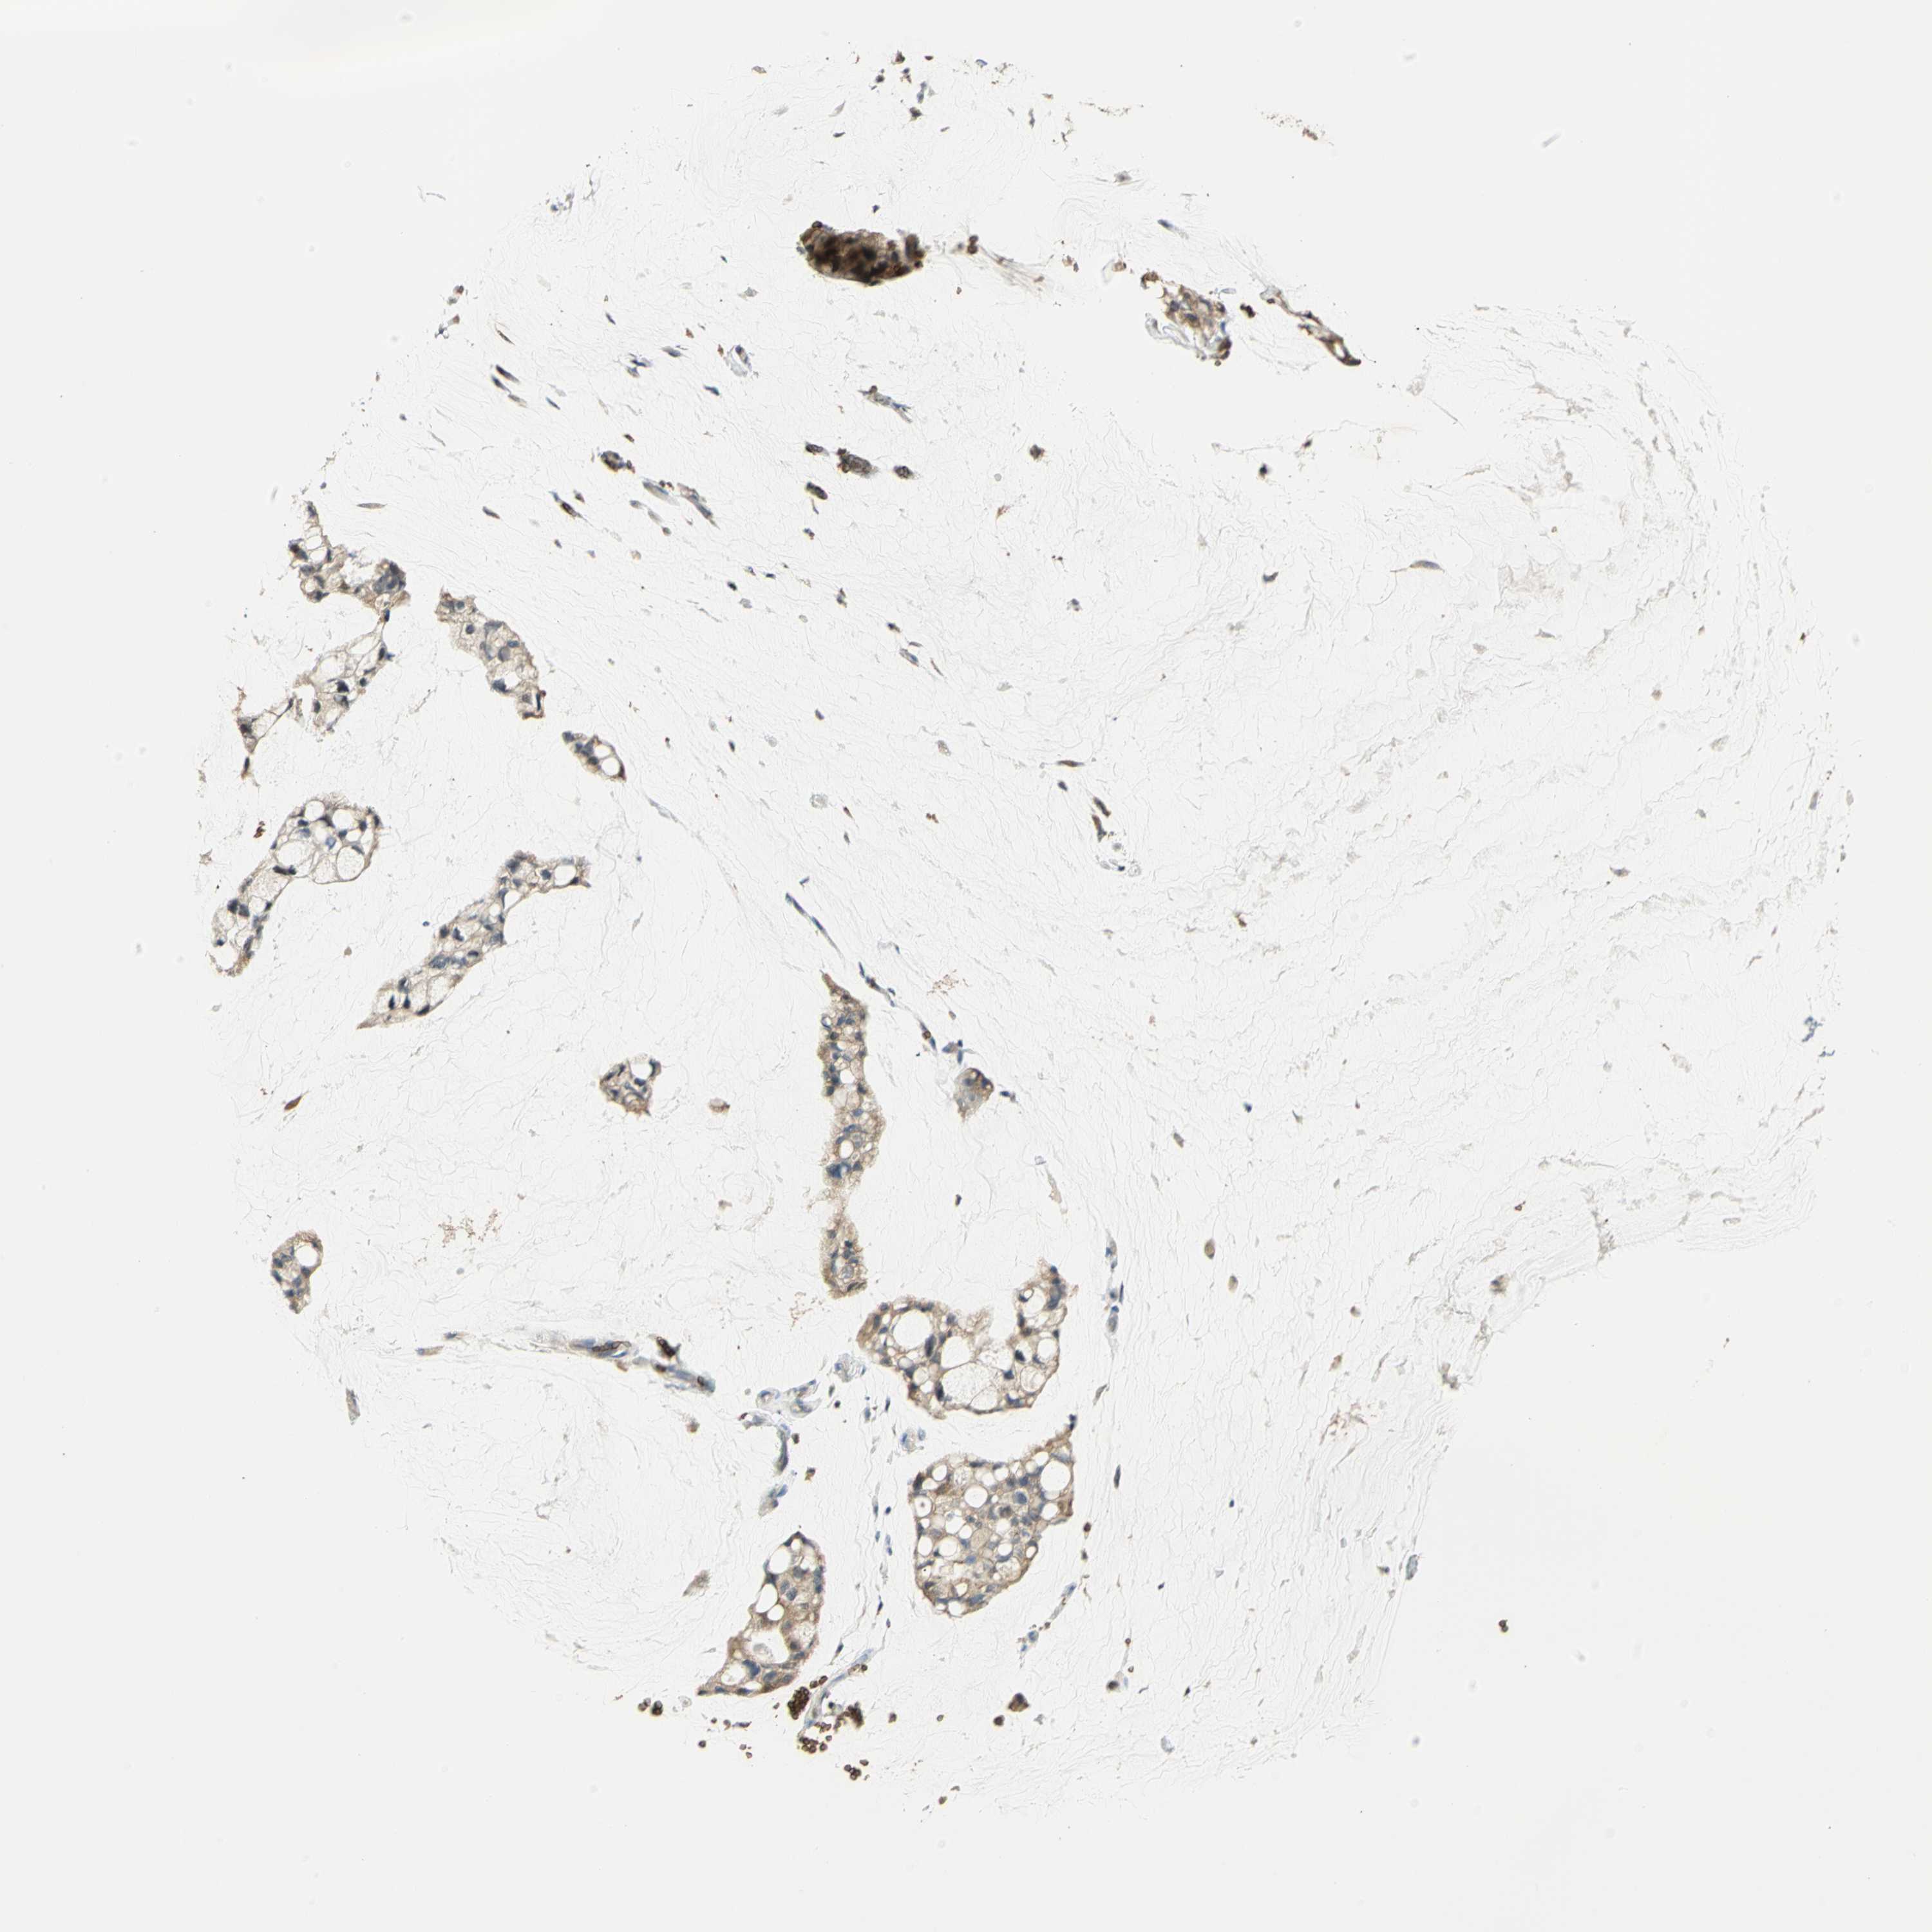

OVARIAN CANCER - Protein expressioni

A mouse-over function shows sample information and annotation data. Click on an image to view it in a full screen mode. Samples can be filtered based on level of antibody staining by selecting one or several of the following categories: high, medium, low and not detected. The assay and annotation is described here.

Note that samples used for immunohistochemistry by the Human Protein Atlas do not correspond to samples in the TCGA dataset.

Antibody stainingi

Antibody staining in the annotated cell types in the current human tissue is reported as not detected, low, medium, or high, based on conventional immunohistochemistry profiling in selected tissues. This score is based on the combination of the staining intensity and fraction of stained cells.

Each image is clickable and will lead to virtual microscopy that enables deeper exploration of all samples and also displays staining intensity scores, fraction scores and subcellular localization as well as patient and tissue information for each sample.

Antibody HPA004842

Antibody HPA056953

Cystadenocarcinoma, serous, NOS

Carcinoma, endometroid

Carcinoma, NOS

Cystadenocarcinoma, mucinous, NOS